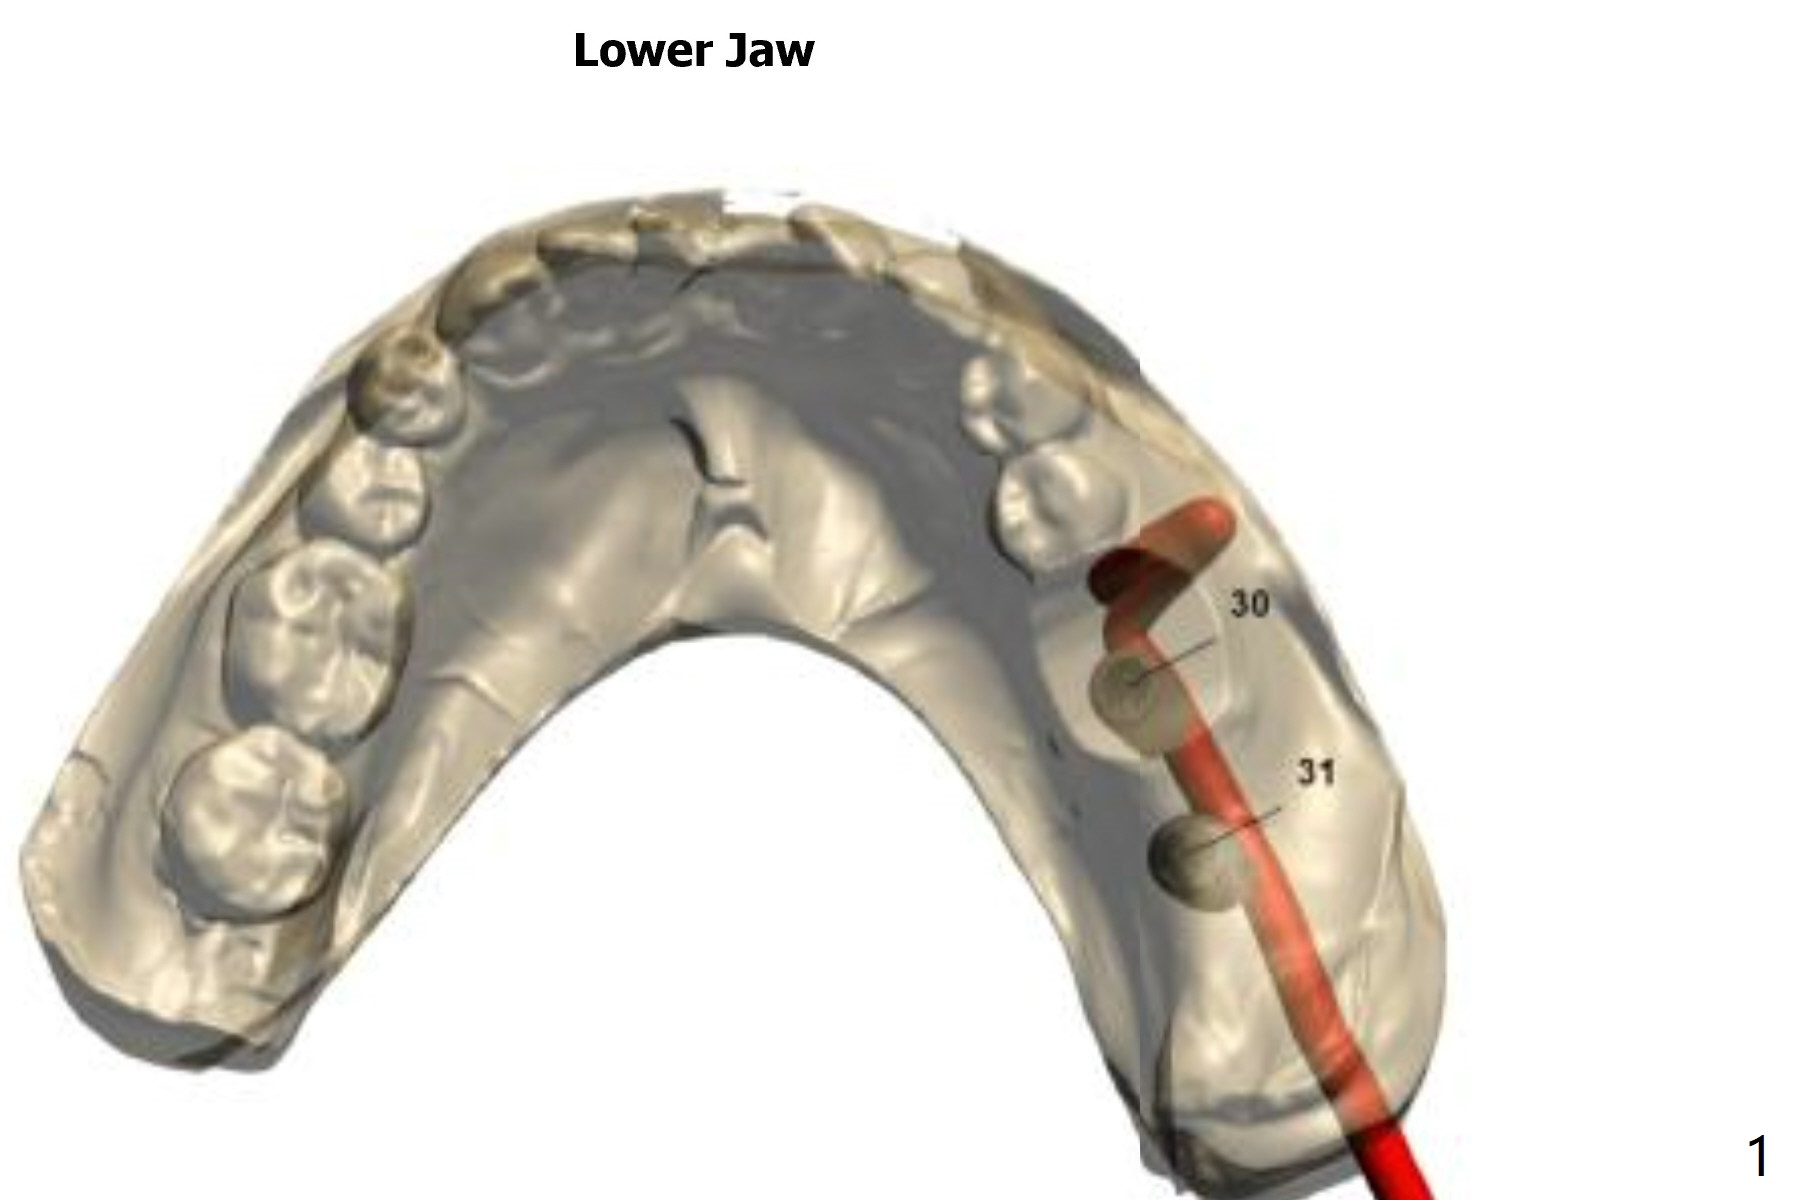

Return to Lower Molar Immediate Implant, Prevent Molar Periimplantitis (Protocols, Table), Trajectory, Clindamycin Xin Wei, DDS, PhD, MS 1st edition 11/30/2018, last revision 01/15/2019